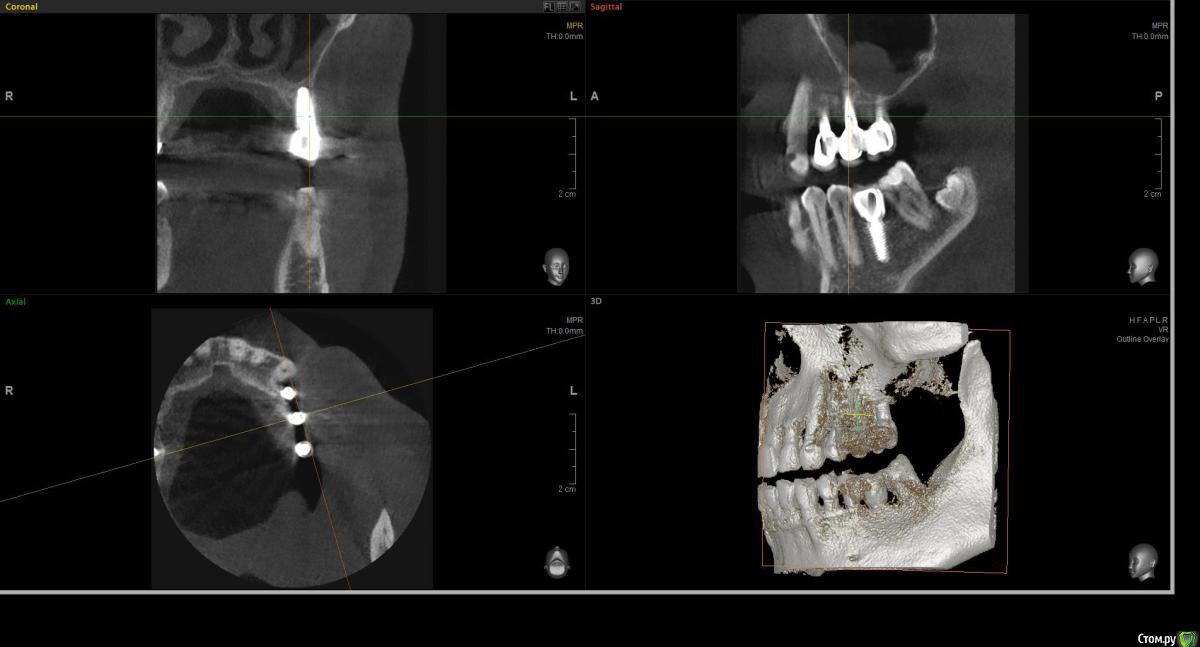

wladdX Опубликовано 20 марта, 2017 Поделиться Опубликовано 20 марта, 2017 (изменено) Несколько скриншотов на скорую руку и снимок из архива, видимо внутриротовая Rg Изменено 20 марта, 2017 пользователем wladdX Ссылка на комментарий

filvik Опубликовано 22 марта, 2017 Автор Поделиться Опубликовано 22 марта, 2017 (изменено) wladdX Спасибо, не знал какие слои выделить.За три года толщина кости уменьшилась где-то на три милиметра.Зубки в коронке стали выше на те-же три милиметра. Изменено 22 марта, 2017 пользователем filvik Ссылка на комментарий

filvik Опубликовано 24 марта, 2017 Автор Поделиться Опубликовано 24 марта, 2017 Как-то, так.К 3-D КТ приложен рентгеновский снимок то, что было в конце в 2013 года, по ниткам резьбыхорошо видна толщина кости в которой сидит дальний имплант (при длине импланта 9 мм.), на КТ 2017 годавидно что с дальней стороны последнего зуба осталось 1,8 милиметра кости.Коронки ставить 1+2 или на каждый отдельно, да и задний имплант похоже держится на честном слове.Вопрос остался прежний что предпринять в данной ситуации? Ссылка на комментарий

filvik Опубликовано 3 апреля, 2017 Автор Поделиться Опубликовано 3 апреля, 2017 подсадка десны трансплантатом с неба наприме...Сходил на совместную консультацию хирурга и ортодонта.1 вариант - подсадка десны трансплантатом с неба не проходит говорят что оголенонесколько витков резьбы на импланте и это не поможет --- предлагают оставить как есть.Хотя перед этим делали подсадку т.к все прогнило до кости и что получилось видно на фото.2 вариант - удалить импланты, нарастить кость , подсадить десну сделать синуслифтинг, установить импланты,поставить формироватили и делать по новой протезирование.В общем говорят что-бы я решал ????????????????????????????????????? Ссылка на комментарий